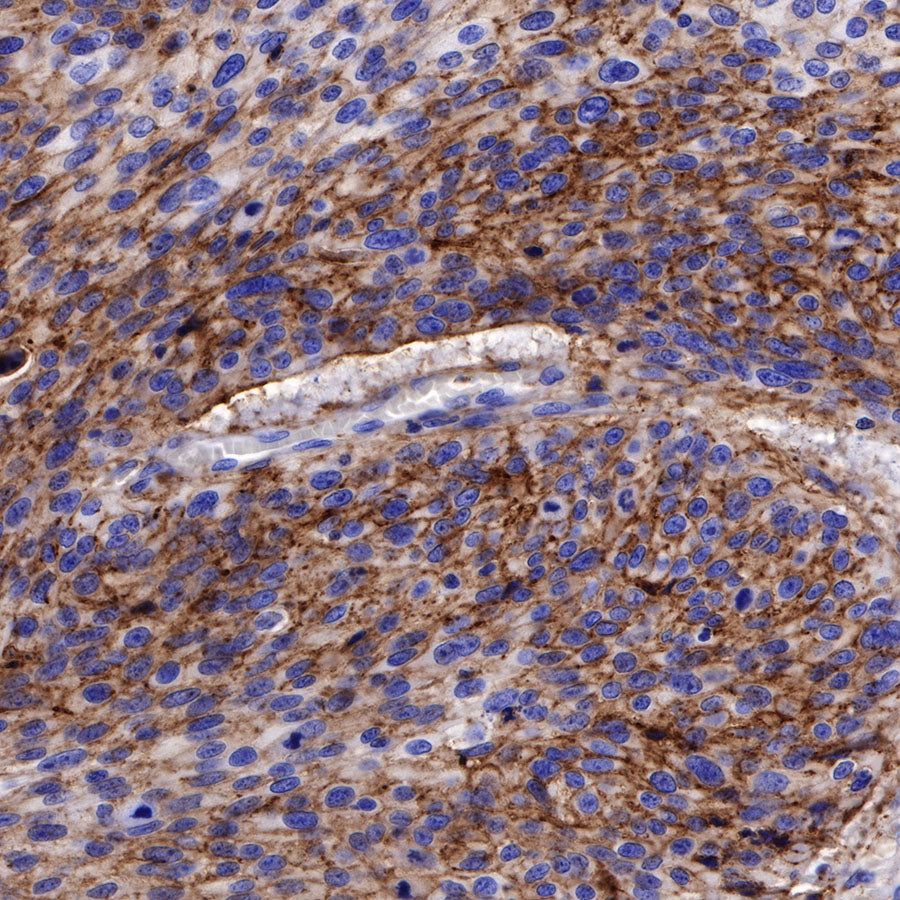

Immunohistochemistry